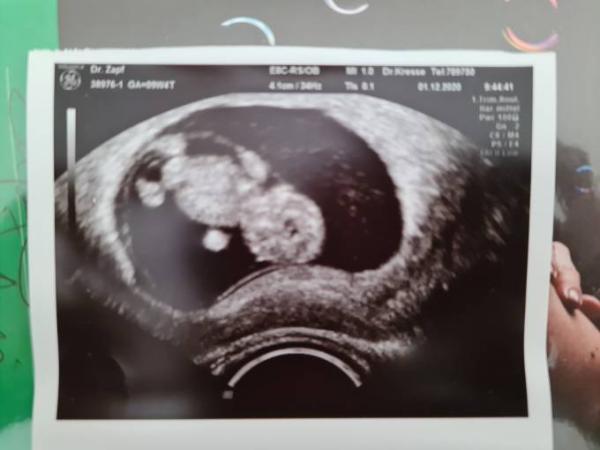

Ich war heute nach 4 Wochen wieder zur Kontrolle beim Frauenarzt. Es war ganz wunderbar! Alles ist zeitgerecht entwickelt, Herzchen schlägt kräftig. Ich könnte nicht glücklicher sein.

Bild zu Heute war FA- Termin - alles super! - Forum für Juli - Mamis

Oh, das ist aber ein tolles Bild! Sieht schon so groß aus! Was ein paar Wochen ausmachen.....